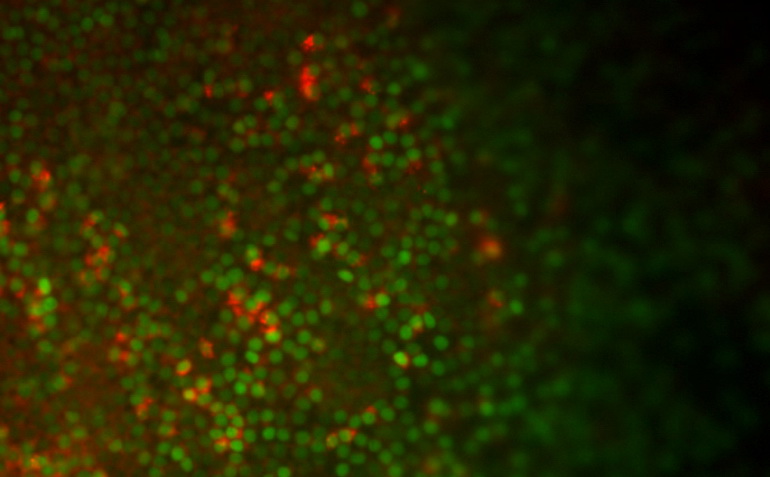

Последнее открытие ученых открывает для них новые возможности, которые позволяют завершить трансформацию человеческих стволовых клеток в функционирующие эпителиальные клетки, расположенные на поверхности легких. Теперь ученые могут создавать как минимум семь типов дыхательных путей, способных выполнять различные функции: начиная от альвеол (маленькие пузырьки на концах дыхательного аппарата в легких, участвующих в акте дыхания) и заканчивая производством клеток, способствующих заживлению повреждений и травм.